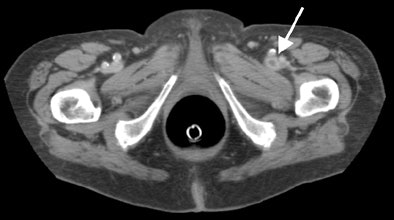

"This is an example of metastasis of ovarian carcinoma to the right psoas muscle," he said of a CT image projected on a screen. "In the same patient we can see thrombosis of the right femoral vein due to compression of this metastasis. The metastasis was successfully treated with surgery and femoral vein with heparin.... This is an example of an aortic aneurysm inflamed with an aortic duodenal fistula, which has been successfully treated in an emergency operation."

| A 76-year-old patient with thrombosis of the left femoral vein that was detected on IV contrast-enhanced CT colonography, and successfully treated with heparin. Image courtesy of Dr. Adrian Spreng and Dr. Hanno Hoppe. |